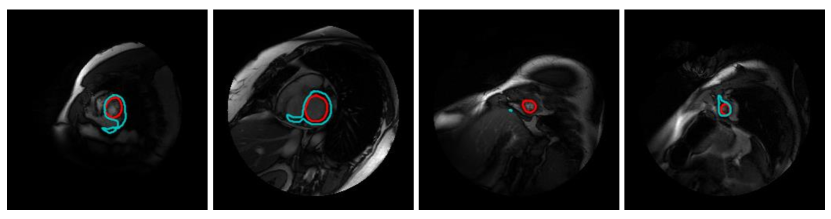

Failure results: As shown in Figure 9, our model has difficulty in segmenting (a) left ventricle with ambiguous or imperceptible boundaries, and (b) the apex and basal regions.

![]() |